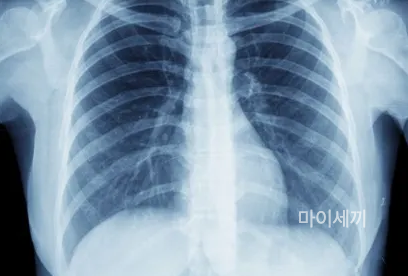

X-ray 검사

폐결핵의 진단은 흉부 X-선 검사를 통해 이루어집니다. 이를 위해 환자의 상태를 확인하고 약물 치료에 사용할 약제를 선택하며, 치료 과정 중에 사용할 약물의 금기 사항을 확인하는 여러 검사가 수행됩니다. 정기적으로 흉부 X-선 사진 촬영과 객담 검사를 반복하여 진행됩니다.